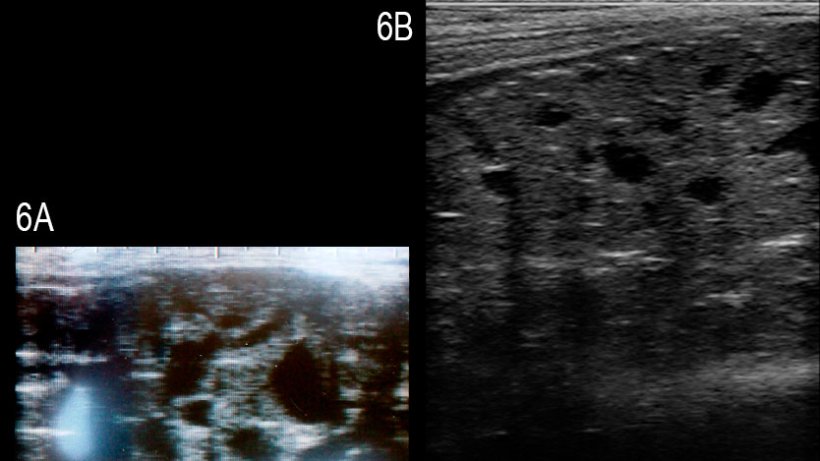

Les études sur l'utilisation pratique de l'échographie dans la reproduction des verrats sont rares. Le diamètre des testicules a été déterminé afin de le relier avec le nombre total de spermatozoïdes produits dans un éjaculat moyen (Clark et al., 2003) ou pour évaluer le développement pubertaire (Ford et Wise, 2010). La corrélation du diamètre des deux testicules et du nombre total de spermatozoïdes a été mauvaise, au moins chez les verrats de plus de 8 mois; la détermination de la taille testiculaire des plus jeunes verrats, d'environ 4 mois, a semblé utile pour la prédiction du volume des testicules et de la production de sperme lorsque le verrat avait atteint la maturité. Il y a un rapport récent sur un verrat Large White infertile avec une dégénérescence multikystique de la glande bulbo-utétrale; dans la glande affectée on visualise des kystes anéchogéniques solides et bien définis de différentes tailles (Figure 6, Grahofer et al., 2016)

Figure 6: Images de la glande bulbo-urétrale d'un verrat atteint par de multiples kystes anéchogéniques bien définis de différentes tailles (A) et d'un verrat sain (B) (Grahofer et al., 2016).